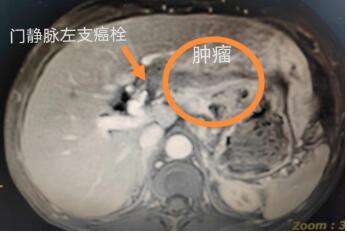

近日,一位来自红河州边疆县的老年男性患者,因“左上腹部疼痛5天”至红河州第三人民医院就诊,急诊行腹部CT检查发现肝脏左叶肿瘤。随后,患者至肝胆外科住院治疗。该科主任徐耀端获悉患者路途遥远、病情紧急,深感患者长途跋涉至该院就诊的艰辛,故立即安排患者入科后第一时间亲自为其诊查,并为其安排和完善相关检查,成功为其实施了腹腔镜解剖性左半肝切除术。